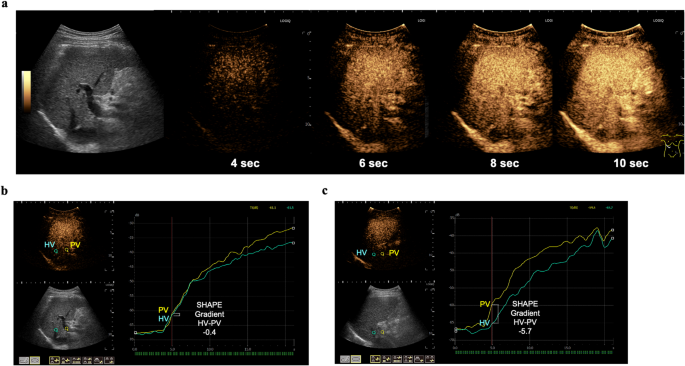

SHAPE examinations were performed under fasting conditions by two experienced sonographers (M.H. and Y.N., with 25 and 15 years of experience, respectively) using a Logiq E10 US scanner (GE HealthCare, Wauwatosa, WI, USA) subharmonic imaging software (research option). The ultrasound probe used was a C1-6-D convex prove with a center frequency of 3.5 MHz. The HV and PV were visualized at the same depth using the right intercostal approach. Perfluorobutane microbubbles (Sonazoid®; GE HealthCare, Amersham, UK), chosen for their superior pressure sensitivity13, were administered intravenously at 0.06 μL/kg. Cine recordings commenced 90 s post-injection, capturing 20-s sequences during breath-hold, with the mechanical index incrementally increased by 0.05 every 0.5 s (Fig. 2a)19.

Representative images (a) B-mode and temporal subharmonic contrast images during the increase of the mechanical index. (b, c) Representative examples of time intensity curve analysis. The SHAPE gradient (HV-PV) values are (b) − 0.4 dB with a HVPG of 12 mmHg and (c) − 5.7 dB with a HVPG of 4 mmHg. HV, hepatic vein; PV, portal vein; SHAPE, subharmonic-aided pressure estimation.

Time-intensity curve analysis was performed using integrated software, with 10-mm diameter regions of interest set at equal depths in the PV and HV. Subharmonic amplitude-acoustic power relationships were derived, and the optimal acoustic power was determined as the maximum slope of the PV response curve12. The SHAPE gradient was calculated as the difference between the HV and PV subharmonic signals (HV-PV) at this optimal power (Fig. 2b, c).